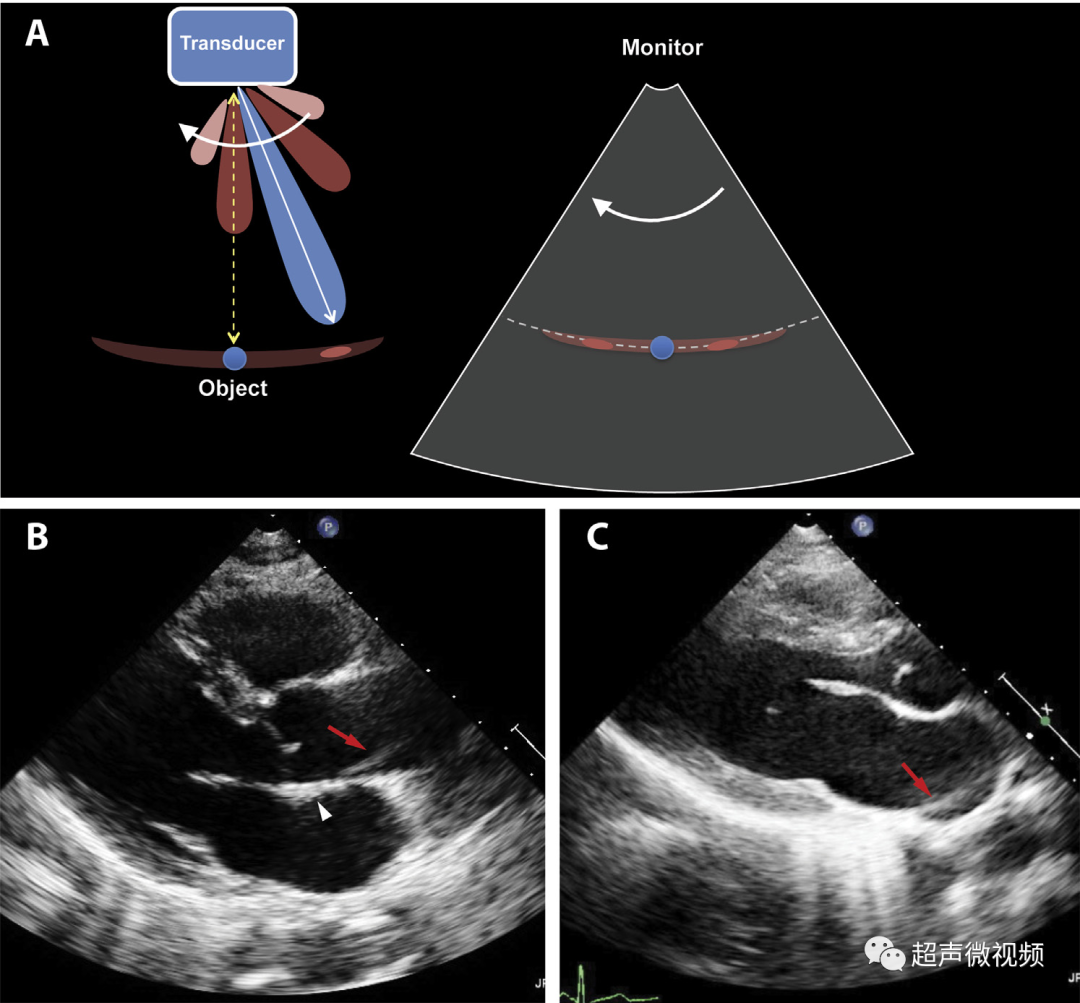

5、旁瓣伪影

在“旁瓣”中发射的一小部分超声能量大部分在组织中消散,而没有相关的反射。

然而,当这种旁瓣能量在其路径上被强反射体(电线、钙化物、心包)反射时,这些反射被扫描仪解释为源自中央波束(违反了“回波来源于探头的主波束”的假设

图5(A) 旁瓣伪影的成因。导致强反射器两侧出现线性“弧形”伪影(视频8)。

(B) 胸骨旁长轴视图,主动脉中有线性旁瓣伪影(箭头),由于钙化的窦(箭头)而上升。这种伪影有时会被误解为解剖皮瓣。

(C) 胸骨旁长轴图显示一名健康患者的心包强烈反射,导致左心房出现旁瓣伪影(箭头)。图像(视频9)、彗星尾混响、声阴影、近场杂波以及二尖瓣叶的镜像也可以观察到。